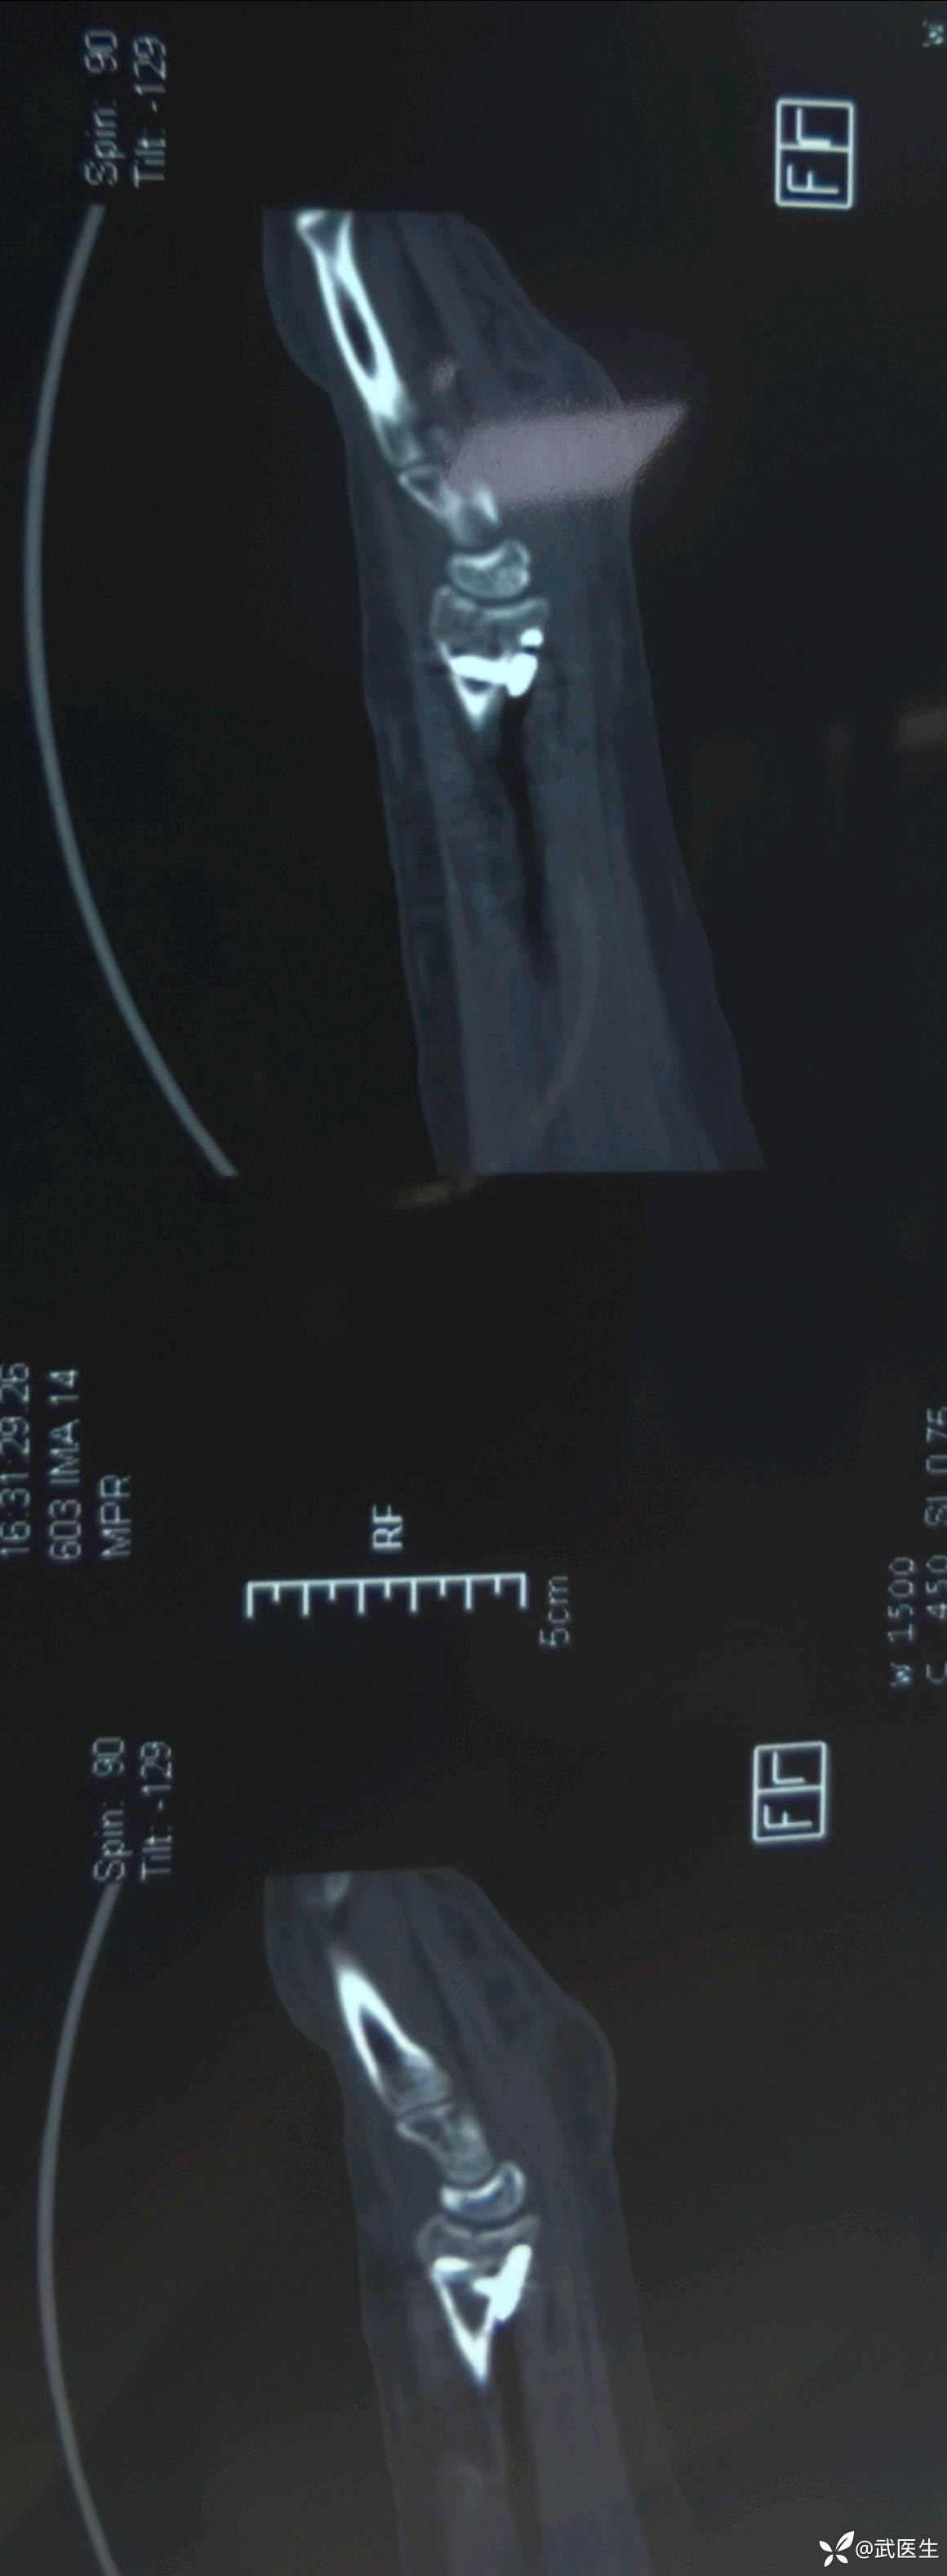

影像学检查如下

腕关节片子系外院带来

【临床诊断】:右肱骨外科颈四部分骨折脱位,左桡骨远端骨折伴桡腕关节半脱位。钩骨骨折。头面部软组织损伤。

术中透视复位良好,术后CT验证一下